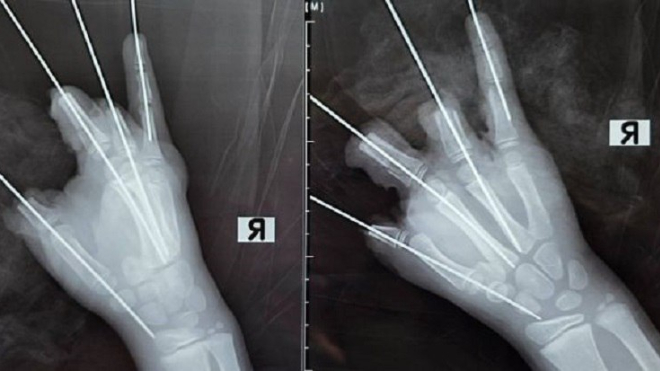

Как рассказали в Педиатрическом университете, взрыв петарды привёл к ампутации четырёх пальцев с большого по безымянный и серьёзным повреждениям мизинца, а также к открытым переломам и вывиху пястной кости. Мягкие ткани кисти были сильно повреждены.

Ребёнка срочно доставили в клинику Педиатрического университета, где врачи незамедлительно провели сложную пятичасовую операцию. Детский микрохирург Антон Волков отметил, что часть тканей сохранить удалось, но реконструировать кисть полностью невозможно из-за серьёзности травмы.

Пациент сейчас находится в реанимации, врачи предупреждают о возможной некротизации некоторых участков кисти в ближайшие дни. Заведующий микрохирургическим отделением Юрий Махин подчеркнул, что такие взрывные травмы у детей нередко приводят к ампутации пальцев, а иногда и всей кисти, и призвал родителей строго соблюдать технику безопасности при использовании пиротехники.